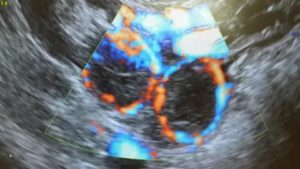

- Кровоток при ЦДК по периферии очень активный. Это неудивительно, ведь временный орган должен хорошо кровоснабжаться для нормальной его работы.

Кровоток по границам желтого тела очень активен, его ткани имеют крайне разнообразное строение, вплоть до формирования кистозных полостей и собственно кист желтого тела.

Практика показывает, что чем лучше выражен кровоток в полости желтого тела, тем большее количество поддерживающего гормона оно способно синтезировать.

На УЗИ с исследованием сосудов можно установить, что сила кровообращения в лютеиновом образовании максимальная в сравнении с остальными органами в женском организме. Сосуды выполняют насыщение каждой клетки железы необходимыми жирами и кислотами.

Васкуляризация работает не только на доставку полезных веществ к желтому телу, но и на отведение синтезированных гормонов.